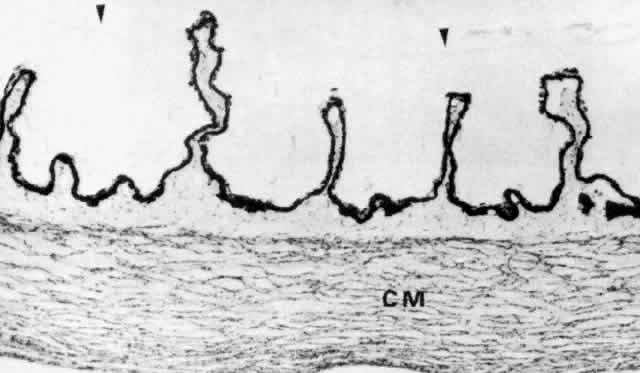

Fig. 30. Pars plicata of the ciliary body cut coronally, perpendicular to the usual

plane. Ciliary muscle (CM) does not extend into the ciliary processes, but

has the same thickness under processes and valleys. The anterior

hyaloid membrane is visible above the processes (arrowheads). (hematoxylin-eosin, X 120) Fig. 30. Pars plicata of the ciliary body cut coronally, perpendicular to the usual

plane. Ciliary muscle (CM) does not extend into the ciliary processes, but

has the same thickness under processes and valleys. The anterior

hyaloid membrane is visible above the processes (arrowheads). (hematoxylin-eosin, X 120)

|